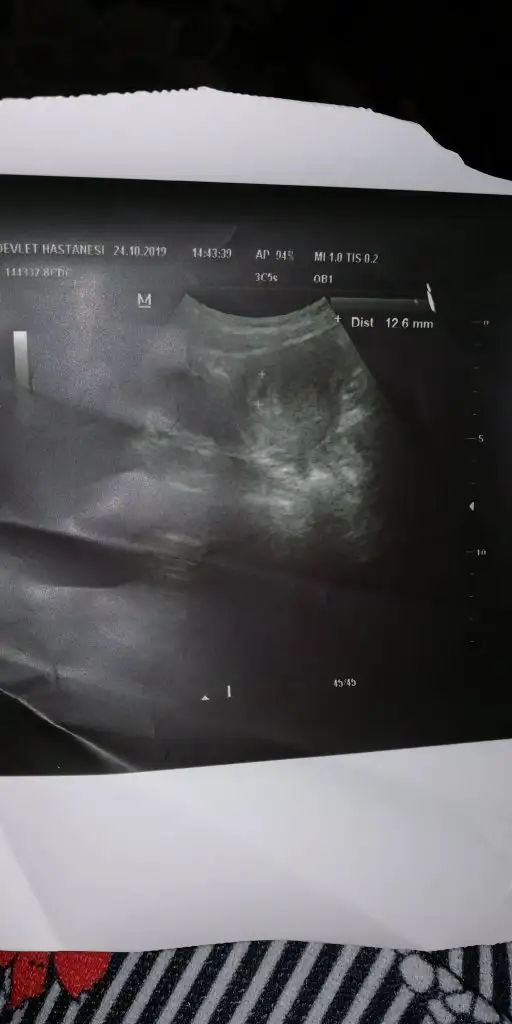

benimde bu şekilde kızlar. sat 13 eylul. dun çekildi bu ultrason 6+1de